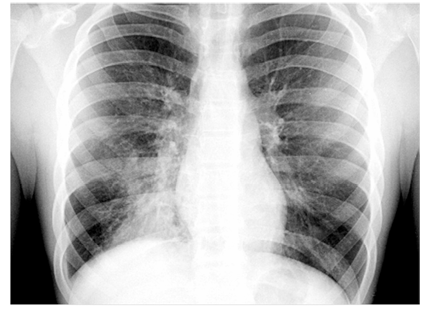

Um paciente de 43 anos de idade, sem comorbidades, alergias ou tratamentos no último ano, apresenta quadro de adinamia, anorexia, picos febris (até 38,5 °C), tosse produtiva com escarro purulento e cansaço aos esforços há dois dias. No exame físico, encontrava-se febril, acianótico, com frequência cardíaca de 108 bpm, frequência respiratória de 21 irpm, saturação de oxigênio em ar ambiente de 95% e pressão arterial de 126 mmHg × 78 mmHg. A ausculta pulmonar revelou estertores crepitantes em terço inferior do pulmão direito. O restante do exame físico não revelou alterações significativas. Os resultados de hemograma realizado indicaram 13.000 leucócitos, sem desvio à esquerda, ureia de 36 mg/dL e creatinina de 0,9 mg/dL. O paciente foi submetido a radiografia de tórax, cujo resultado está apresentado a seguir.